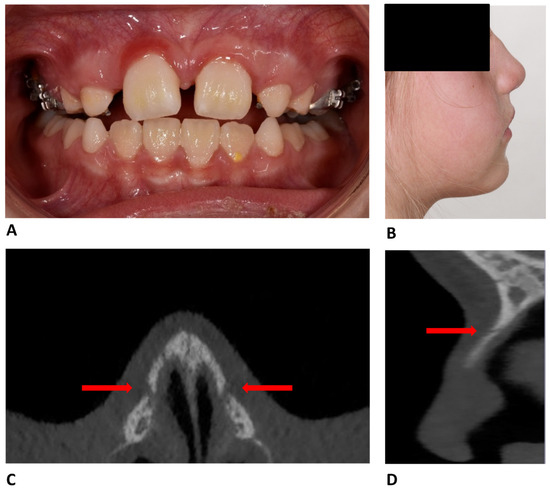

Nasal Fracture During Maxillary Expansion—A Rare Complication?

by Katharina Obermeier, Wenko Smolka, Philipp Poxleitner, Natasa Puskar and Hisham Sabbagh

Reports 2026, 9(2), 108; https://doi.org/10.3390/reports9020108 - 1 Apr 2026

Background and Clinical Significance: This case report describes an unusual complication in an 8-year-old female patient undergoing ME (maxillary expansion) with a tooth-supported maxillary expander with the hyrax screw. Case presentation: After the 36th screw turn in the 5th week of treatment, the [...] Read more.

Background and Clinical Significance: This case report describes an unusual complication in an 8-year-old female patient undergoing ME (maxillary expansion) with a tooth-supported maxillary expander with the hyrax screw. Case presentation: After the 36th screw turn in the 5th week of treatment, the patient reported pressure and pain symptoms and the patient’s parents observed a bone elevation at the bridge of the nose. The patient was referred to for clinical examination which revealed a bilateral infraorbital hematoma and a movable, and highly sensitive, nasal area upon palpation. A cone-beam computed tomography (CBCT) scan confirmed a displaced nasal bone fracture. Conservative treatment was immediately initiated by reversing the hyrax screw four times, followed by ten additional turns over the next 7 days for a total of 14 back-turns. This procedure led to an immediate improvement in symptoms. An 8-week follow-up CBCT confirmed the physiological repositioning of the nasal bones and healing of the fracture. Conclusions: Although nasal bone fracture is a rare complication of ME, particularly in children, clinicians should be aware of this potential risk and remain vigilant for symptoms of high pressure and pain in the orbito-nasal area. If a nasal fracture is suspected during orthodontic treatment, the orthodontist should immediately cease screw activation. In selected cases, careful reversal of the screw, as described in this report, may be considered as a conservative treatment. Full article